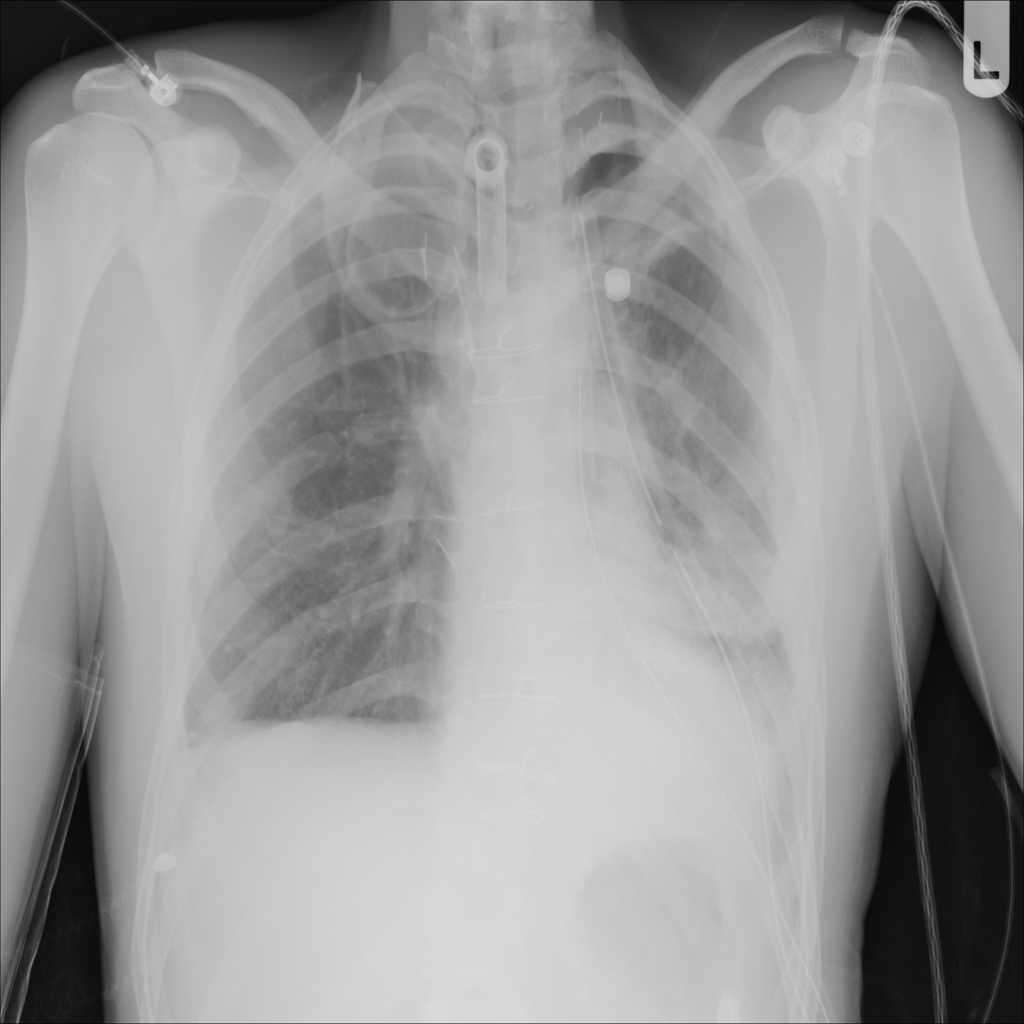

PAT-4639 · IMG-012Pneumothorax

PAT-4639 · IMG-012

AP